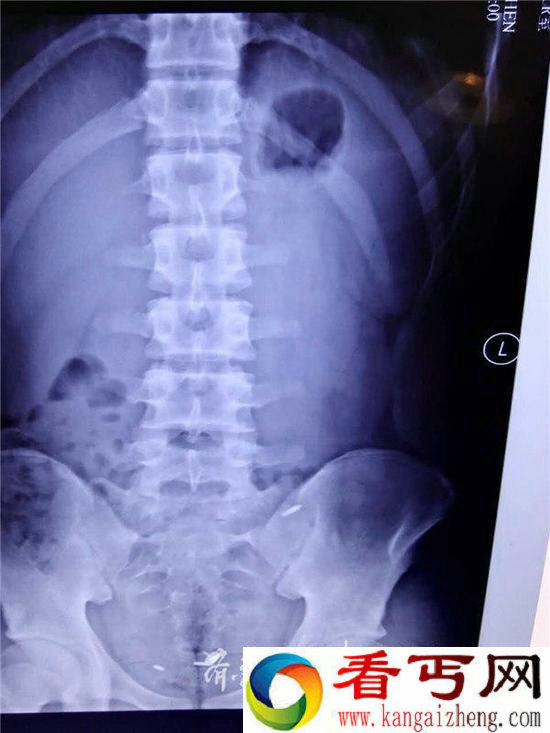

与同学打赌吞图钉,医生用了将近5个小时的时间才将3个圆珠笔芯的芯头从肚子里取出。究竟是为什么要与同学打赌吞图钉呢?

与同学打赌吞图钉,医生用了将近5个小时的时间才将3个圆珠笔芯的芯头从肚子里取出。究竟是为什么要与同学打赌吞图钉呢?7月8日,齐鲁医院急诊外科的医生用了近5个小时的时间,才把小赵(化名)肚子里的3个圆珠笔芯金属芯头全找到;就在当天早上,小伙子还自行排出一枚图钉!家属告诉医生,孩子是因为和同学打赌才做出如此行为,但拒绝接受采访。